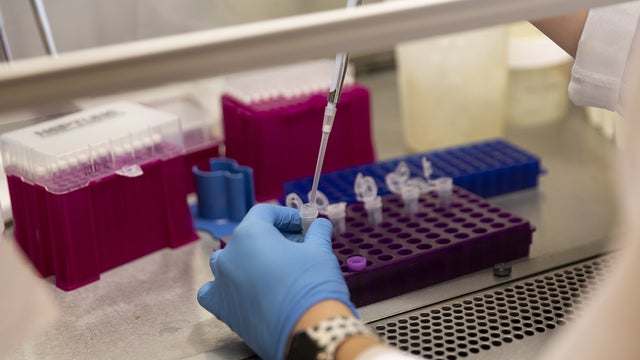

Maryland Researchers Asking For More People To Take Part In COVID-19 Vaccine Trials

Researchers are hoping for more participants to come forward to take part in coronavirus vaccine trials.

Researchers are hoping for more participants to come forward to take part in coronavirus vaccine trials.